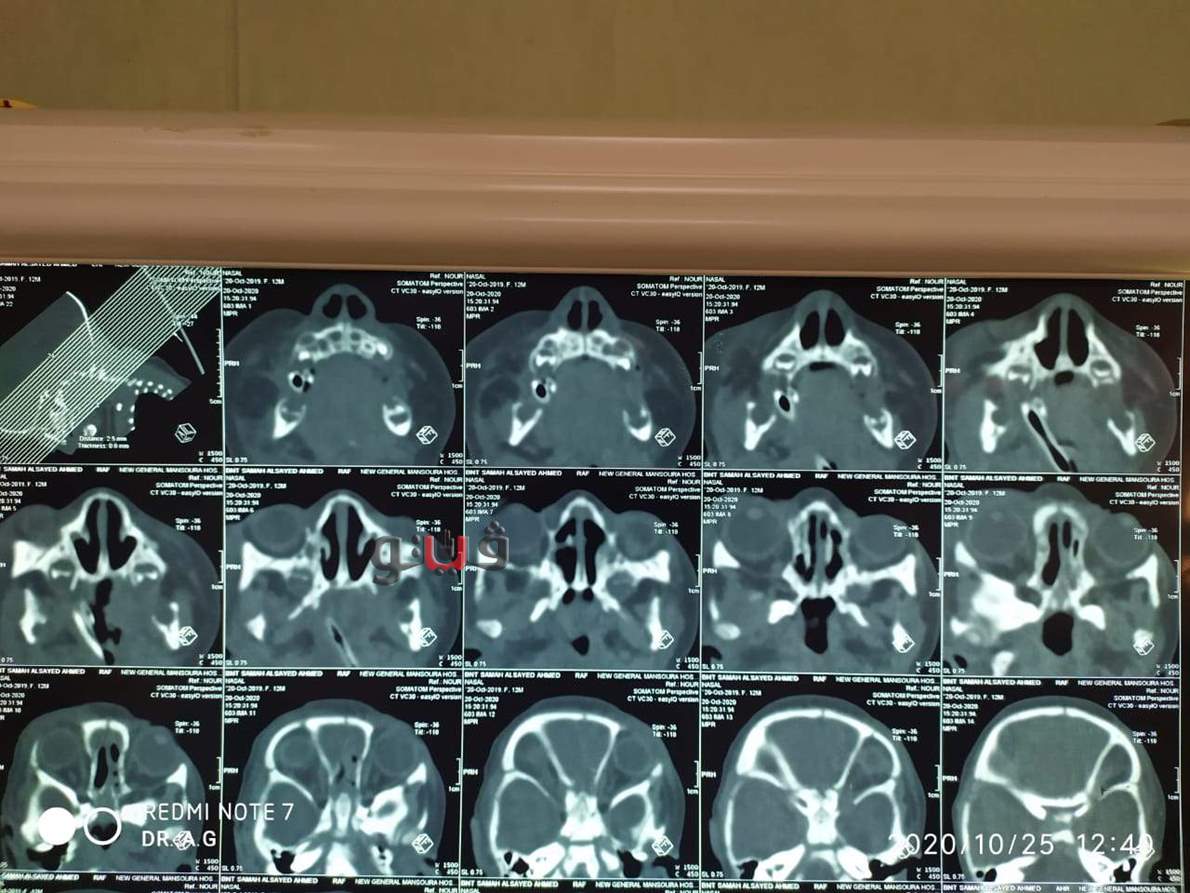

أعلن الدكتور سعد مكى وكيل وزارة الصحة بالدقهلية عن نجاح فريق طبي بمستشفى المنصورة العام الجديد، بإصلاح عيب خلقي لرضيعة تبلغ من العمر 6 أيام كانت تعانى انسدادا بعظمتي الأنف بالناحيتين وانسدادا بمجرى الأنف وصعوبة تامة بالتنفس وهي حالة نادرة الحدوث.

وأوضح أنه تم التدخل الجراحي السريع لإصلاح العيب الخلقي بواسطة فريق طبي مكون من كبار استشاريي الأنف والأذن والحنجرة حيث تمت العملية بنجاح باهر وخرجت الطفلة من العمليات بحالة مستقرة.